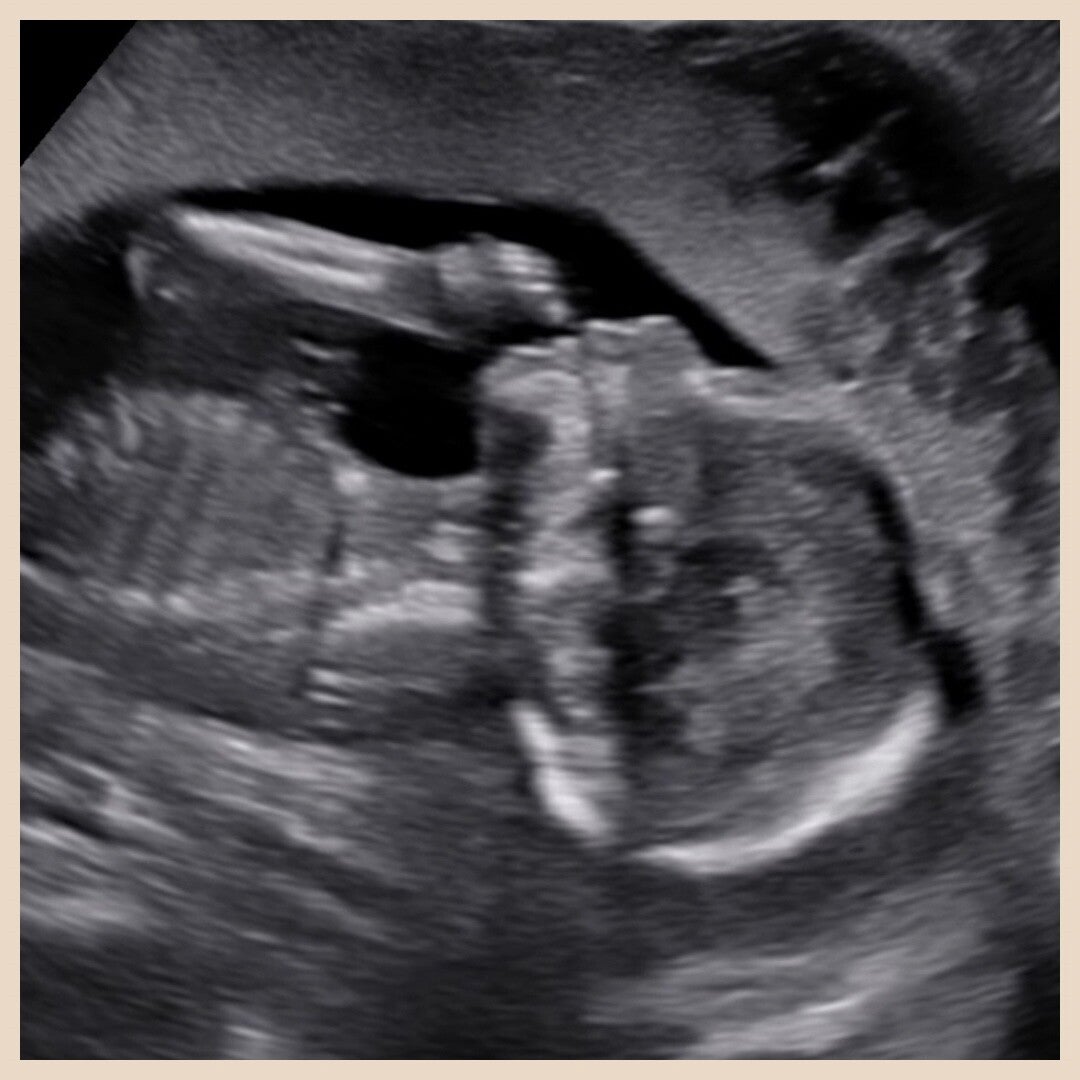

Deze echobeelden (maar ook alle andere plaatjes op deze website) zijn door Pretecho Thuis gemaakt!